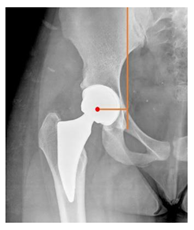

Plain radiographs were evaluated preoperatively and at the most recent follow-up, after appropriate calibration. Positional parameters were assessed according to values guidelines from published literature, as listed in Table 1 [23,24,25,26,27,28,29,30,31]. Femoral stem and acetabular cup osteointegration were quantified according to Engh [32] and Moore scale [33]. Heterotopic ossifications were graded according to the Brooker system [34].

3.4. Radiographic Evaluation

Preoperative and postoperative radiographic data are reported in Table 4. Preoperatively, 18 THR (24.3%) were implanted in skeletally immature children with closed triradiate cartilage (1 ≤ Risser ≤ 3). Radiographic acetabular insufficiency (LCEA < 25° and AI > 13°) was detected in 14 hips (18.9%), while protrusion was present in 3 hips (4.1%) An excessive valgus of the femoral neck was observed in 19 hips (25.7%), while an important varus deformity was present in 7 hips (9.5%).

Postoperative radiographs showed a significant vertical malposition of the cup in 1 case (1.4%), a significant varus stem in 8 cases (10.8%) and a significant valgus stem in 1 case (1.4%). Two patients (2.7%) showed moderate heterotopic bone formation (Brooker ≥ 2), that did not significantly affect the hip motion and symptoms. All those THR that did not undergo revision showed good radiographic osteointegration, with no evidence of implant breakage, radiographic lucencies, bone defects, cup migration, or stem subsidence at the most recent radiographs.

In our experience, implant malposition was the only reason for implant revision. In one case, progressive subsidence was observed in a varus undersized stem, implanted in a boy with Albers–Schömberg disease; in another case, an excessively vertical cup with a 28 mm femoral head caused hip instability and required cup revision.

THR can be a challenging procedure in very young people. The combination of distorted anatomy, small physique, and poor bone stock can impede proper implant placement. Implant sizing may be an issue in these patients. The combination of young age and peculiar conditions such as skeletal dysplasia may require particular attention in preoperative planning and implant selection. Noticeably, we used the smallest size of the cup in 11 hips (15%) and the smallest size of the stem in 14 hips (19%). A meticulous preoperative planning, even using simulation software, [40,41,42] and careful implant selection, sometimes requiring even customized implants [37], is crucial in such conditions, to prevent unpleasant pitfalls during the operation.